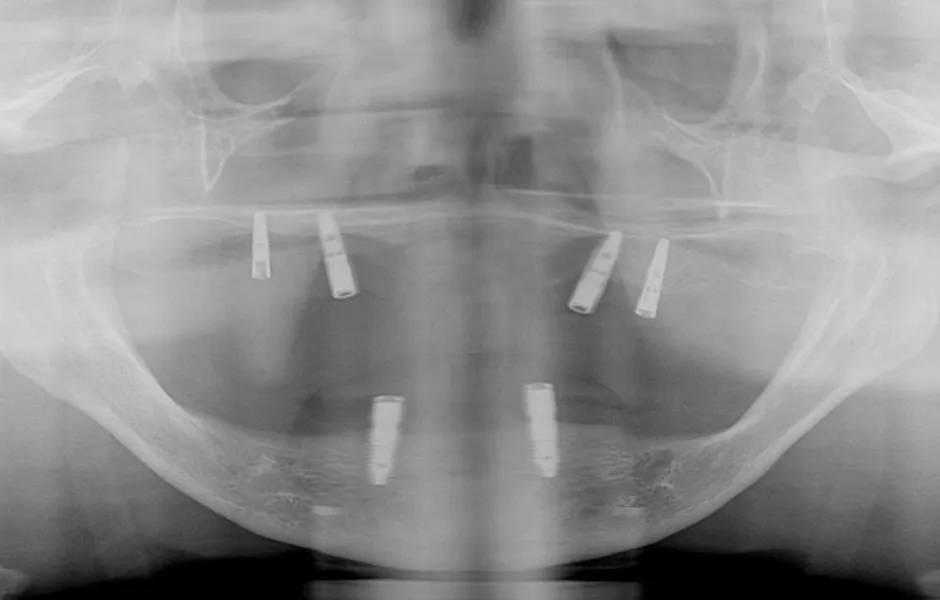

インプラント治療

失った歯を補う方法の1つで、インプラントが歯根の代わりを果たすことで天然歯に近い噛み心地を再現します。当院ではサージカルガイドを使用することで、より精密な埋入を可能とし、術後の痛みや腫れを軽減しています。機能性だけでなく審美性も回復します。

オールオン4・6

歯をすべて失っている方にインプラントを4~6本埋入して、連結した人工歯を支える治療法です。手術回数と埋入数が少ないので、患者さまの体への負担と費用を軽減できます。